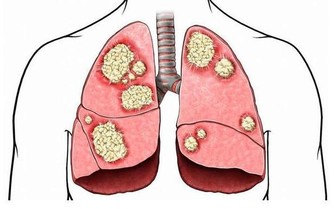

3、在抬腳時可引濁氣下行排出,升清降濁正氣倍增,體內正常細胞大曾活躍,癌細胞自然死亡。